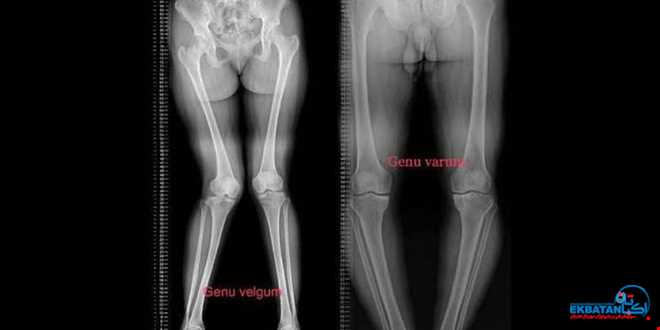

پا پرانتزی (Genu Varum) و پا ضربدری (Genu Valgum) از شایع‌ترین ناهنجاری‌های محور اندام تحتانی در کودکان هستند. اگرچه این تغییرات گاهی بخشی طبیعی از رشد محسوب می‌شوند، اما در برخی موارد می‌توانند به دلیل مشکلات تغذیه‌ای، بیماری‌های استخوانی یا اختلالات رشد ایجاد شوند. تشخیص زودهنگام این تغییر شکل، کلید پیشگیری از آسیب‌های مفصلی در آینده است.

رادیوگرافی الاینمنت یا تصویربرداری تری جوینت، تکنیکی تخصصی برای بررسی دقیق محور مکانیکی پا از لگن تا مچ پا در حالت ایستاده است. در این روش سه مفصل اصلی:

در یک تصویر بلند (Full-Length) ثبت می‌شوند تا پزشک بتواند زاویه‌ها و محل انحراف محور مکانیکی را به‌وضوح ارزیابی کند.